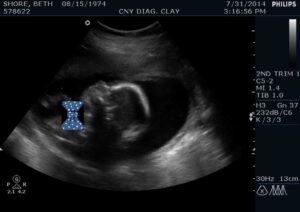

As the pregnancy progressed, we decided we really wanted to know if this baby was a boy or a girl. I felt so different that I was convinced it was a girl. The day we had the ultrasound done, the technician was put in the interrogation room. I shined that light directly in her eyes and demanded things like, ‘Does the baby look okay?’ ‘Is everything normal?’ My fear of Down syndrome had not subsided and anxiety twisted knots inside me. It seems my interrogation tactics were not as scary as I thought. The only response I was gifted was, ‘Only the doctor can really tell. You’ll discuss it at your next appointment…’ and she definitely could tell the sex. She handed me my secret in an envelope and sent us on our way. The way she said it made me think I was having a boy and what she didn’t say kept my fears alive.

So, there was the day. I was reunited with my old doctor and it was like we didn’t miss a beat. We got right back into our old flow where I did all the talking and he smiled gently telling me all was fine. Then, I said it. ‘Doc, I’m really worried about Down syndrome. Do you see anything in the ultrasound from my other doctor that would suggest it?’ I was met by an eager no and an inspection after. He said he didn’t see a thing but suggested I get another ultrasound just to be sure. As I trotted to the scheduling desk, we went back and forth trying to secure a date. That’s when the ultrasound tech walked by. Perfect. She was available right then.

I walked in and we watched my baby, in 4D no less, moving and we celebrated him being cute. We giggled at him, she confirmed he was most certainly a boy (cue little stomach drop again) and then… ‘did you have the genetic testing done?’ I went into full blown panic mode. My cheeks got hot, mouth dry and how did all of the sudden my tongue get too big for my mouth? I said no. I asked if she saw something. She replied, ‘not outwardly’… well, that’s a crappy answer.